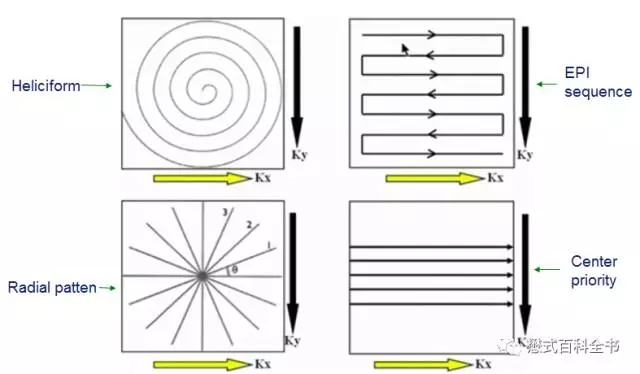

这一部分我会在后面参数的故事(五)中讲到。我们前面讲了这么久的K空间,为了方便大家理解,我们都默认为K空间是遵循一种线性的次序填充的方式,也就是一条相位编码线填充完,再填充下一条线,再下一条,以此类推.....

我们前面知道,K空间是存储磁共振原始采集数据的空间,利用K空间中的数据我们可以重建磁共振图像。那么只要保证K空间里的数据足够我们就能够得到磁共振图像。也就是不管用什么方式,只要保证K空间中填充有足够的数据就可以,所以我们可以并不拘泥于这种线性填充方式。我们还可以变换各种花样来填充K空间。

图16:不同轨迹的K空间填充方式

有的老师可能会问,好好的线性填充方式,为什么要变换花样填充K空间呢!不同的K空间填充方式会有不同的作用。

比如,采用放射状的填充方式,我们可以看到,每一次填充完一条相位编码线,相位编码梯度变化,旋转一下角度,再填充下一条相位编码线,这样的话,K空间中心部分会被反复的重复填充。因为K空间中心部分主要决定对比度,所以,通过这种方式填充,可以消除部分运动伪影。